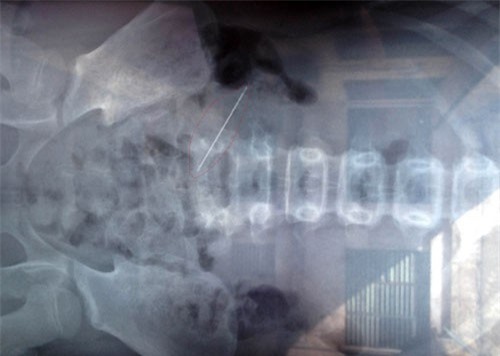

Trong suốt nhiều năm kể từ sau lần mổ đẻ tại BVĐK huyện Can Lộc (Hà Tĩnh), chị Hòa thường bị đau đầu, chướng bụng, huyết áp cao. Trong một lần đi chụp X-quang, chị Hòa choáng váng khi biết, dưới vết mổ cũ trong bụng có 1 chiếc kim khâu mà bác sĩ để "quên" 9 năm nay.